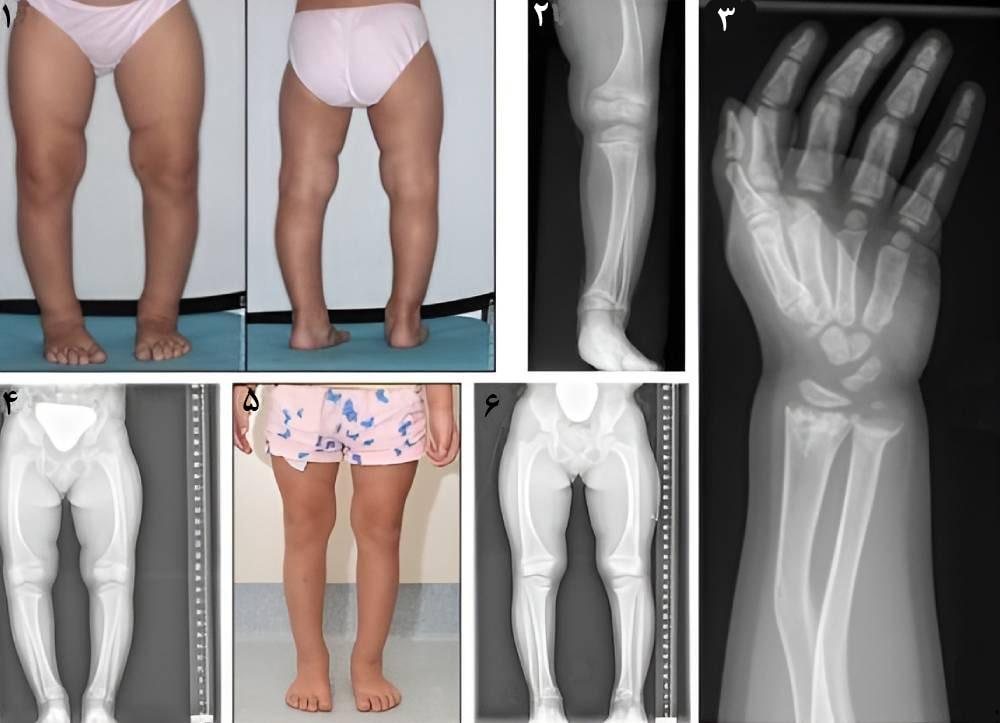

- پای پرانتزی

- زانوی ضربدری

- عکسبرداری: پزشک با عکسبرداری میتواند از تغییر شکل و انحراف استخوانها آگاه شده و میزان ناهنجاری آن را بررسی کند.

اگر نرمی استخوان در کودکان درمان نشود و کودک به سن بلوغ برسد، صفحات رشد بسته میشوند و ناهنجاریهای ناشی از راشیتیسم که شامل ناهنجاریهای دست و پا است به طور دائم باقی میماند. همچنین اگر فرد بزرگسالی به مدت طولانی به استئومالاسی مبتلا بوده و برای درمان آن اقدام نکند ممکن است به ناهنجاری استخوان دچار شود. در این موارد فقط درمان با مکملهای ویتامین و مواد معدنی برای رفع ناهنجاریهای ناشی از نرمی استخوان کافی نیست و بیمار برای رفع عوارض دائمی ناشی از این بیماری نیاز به درمانهای دیگر نیز دارد.

- جراحی اپی فیزیودز (Epiphysiodes): این جراحی معمولاً برای کودکانی که زیر سن بلوغ هستند برای جلوگیری از کج شدن استخوان در محل صفحات رشد انجام میشود. این یک جراحی کمتهاجمی بوده و با حداقل برش و خونریزی انجام میشود. پزشک در این جراحی با ایجاد چند برش کوچک روی پوست، بخشی از صفحات رشد استخوان را با نوعی بست و پیچ میبندد، این کار باعث هدایت رشد استخوان در موقعیت صحیح خود در مراحل درمان راشیتیسم میشود.

- جراحی استئوتومی (Osteotomy): در این جراحی که بیشتر بعد از سن بلوغ توصیه میشود پزشک بخش ناهنجار استخوان را برش میدهد و آن را در موقعیت صحیح با پیچ و سیمهای مخصوص میبندد. پای بیمار بعد از جراحی گچ گرفته میشود و تا زمان جوشخوردن استخوان بیمار نباید راه برود. پس از ۶ تا ۸ هفته گچ را باز میکنند و بیمار ممکن است به چندین جلسه فیزیوتراپی بعد از جراحی نیاز داشته باشد.

- ناهنجاری استخوان پا و دست

راشیتیسم معمولاً روی استخوانهای بلند بدن تأثیر میگذارد و اغلب موجب ناهنجاری استخوانهای ران، ساق پا، استخوان ساعد و قفسه سینه میشود.